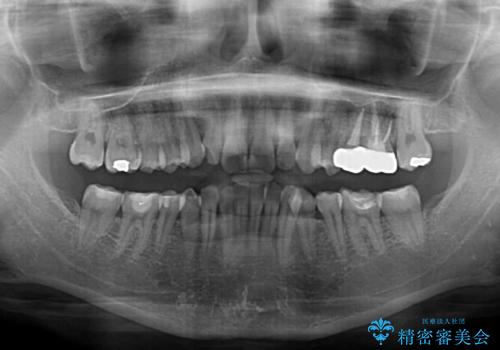

- 下顎の前歯が隠れていることと、デコボコを気にして来院された患者様です。

銀歯やムシ歯処置の必要な歯が奥歯にあり気になっていたので、矯正治療の途中でセラミッククラウンへ変更し、その後歯列を仕上げていくこととしました。

咬み合わせと目立っていた銀歯が改善され、患者様には大変満足していただきました。